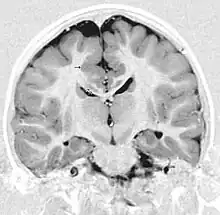

Gray matter heterotopia

Gray matter heterotopia is a neurological disorder caused by gray matter being located in an atypical location in the brain.[1]

Gray matter heterotopia are common malformations of cortical development known as neuronal migration disorders. Heterotopias are classed in two groups: nodular and diffuse. Nodular types are subependymal and subcortical; diffuse types are termed band heterotopias. Affected patients are generally divided into three groups, depending on the location of the formation: subependymal, subcortical, and band heterotopia. In addition, especially with heterotopia that are genetically linked, there are sex differences. Men seem to develop more severe symptoms than women with similar formations.